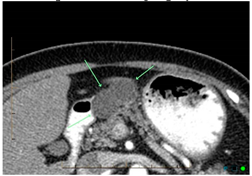

Computed tomography (CT)![]() | High sensitivity and specificity (76–92% and 67% respectively) Standardized available protocol- pancreatic protocol CT Multidetector CT Good spatial and temporal resolution Lower cost and greater availability | Radiation exposure with the risk of secondary cancer attributable to the CT procedure Performance depends on ability to administer intravenous Iodine contrast Allergies to CT contrast agents (common) Cannot detect iso-attenuating PDACs with indistinct borders and small pancreatic tumours |

Endoscopic ultrasound (EUS)![]() | High sensitivity and specificity (72% and 90% respectively) Excellent resolution for small lesions Mainly used as part of the work-up to obtain biopsy (FNA) for tissue diagnosis | Performance varies by disease T stage Invasive procedure, not practical for routine follow-up Not readily accessible imaging modality Highly dependent on technical skill of the operator Limitations for evaluating solid pancreatic lesions Procedural risks |

Magnetic resonance imaging (MRI)![]() | Highest sensitivity and specificity (93% and 89% respectively) Better soft tissue resolution No radiation exposure Better at determining metastasis Better accuracy for assessing local involvement of a pancreatic lesion | Can be difficult to obtain in patients with claustrophobia, metal devises, or allergies to gadolinium (very rare) |